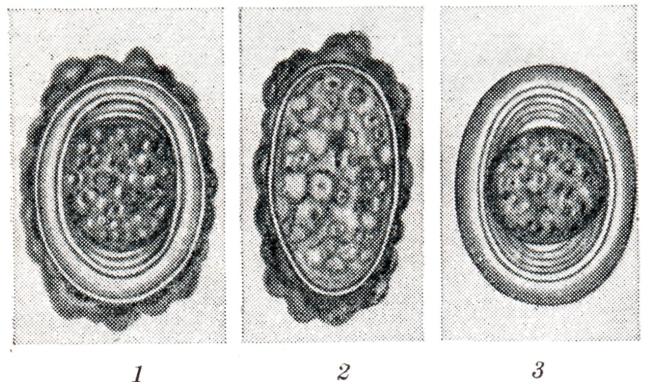

При попадании такого яйца в кишечник человека личинка освобождается от яйцевых оболочек, проникает в толщу слизистой оболочки и подслизистой основы и внедряется в кишечные вены, по которым попадает в воротную вену. По внутридольковым капиллярам личинка проникает в центральные вены печеночных долек, затем в поддольковую вену и через крупные венозные стволы — в нижнюю полую вену. По нижней полой вене она попадает в правое предсердие, затем правый желудочек и через легочный ствол — в капилляры альвеол, а затем в просвет последних (рис. 3). До выселения в воздухоносные пути личинки могут проникать из легочных артерий в вены, затем через левое сердце в большой круг кровообращения и током крови заноситься в разные органы. Буравящая способность личинок при этом утрачивается, и они не могут вернуться в кровеносное русло, постепенно инкапсулируются и погибают. |

Рис. 3. | ||